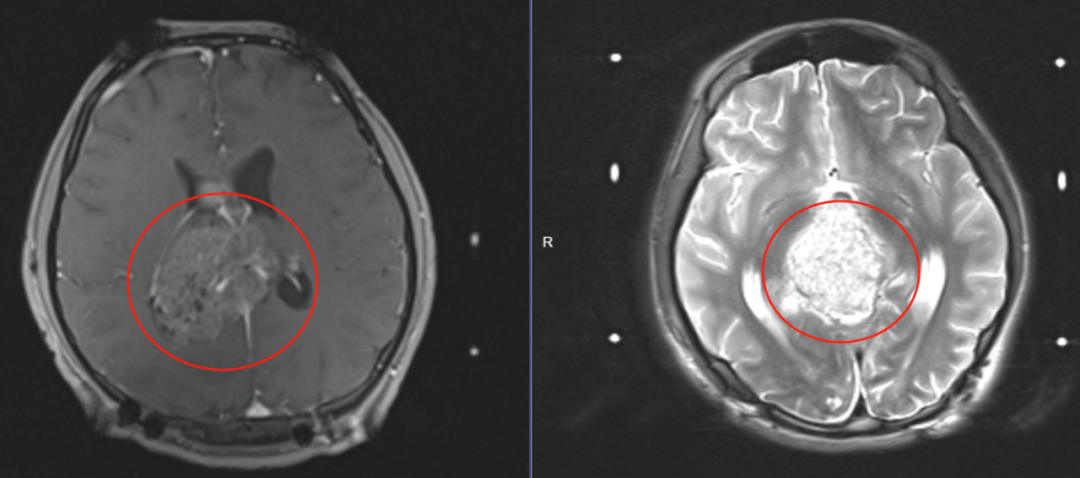

青春勃发的帅气少年嗜睡多日 不幸查出恶性脑瘤 6个月前,正在读初中的李建国(化名)因嗜睡,言语不清等症状不得以中断学业,去医院全面检查后确诊为松果体恶性肿瘤,并随即进行了脑瘤切除手术,术后需要进一步辅助放疗才能清除颅内肿瘤难以切除的残存病变。 经过多方打听,他父母了解到昆明医科肿瘤医院余小平主任团队及骆建华主任团队在颅内恶性肿瘤的治疗方面经验丰富,便慕名前来寻求治疗方案。 精准放疗 逆转危机 让生命之花重新绽放 李建国(化名)刚来医院时,全身颤抖,嗜睡情况也不容乐观,通过余主任团队与骆主任团队对病情的全面评估后,决定采用先进的立体定向放疗技术——伽玛刀放射治疗与常规放疗相结合进行治疗,通过第一次伽玛刀治疗后,嗜睡多日的李建国(化名)当日即可下地独自上洗手间,妈妈叫他也可以正常回应了。 自从孩子生病后,他妈妈每日都在煎熬中度过,看着眼前的李建国(化名)就像没生病以前的正常状态,妈妈激动地留下眼泪,拉着余主任、骆主任和医护人员说:“太感谢你们啦,我儿子有今天这个正常状态,多亏了你们悉心照顾和余主任的精湛医术,能找到你们团队,真的是我们家不幸中的万幸......” 通过科学、规范、合理的治疗,李建国(化名)各项身体指标都倾向好转,顺利出院! (治疗前2023年10月影像资料) (治疗后2024年2月复查影像资料 显示肿瘤消失) 字字显真情 句句赞医心 一封感谢信承载着浓浓医患情 出院后,医院医疗服务部经常通过电话或微信关心李建国(化名)的身体状况,并叮嘱他生活中的一些注意事项及复查提醒。 “在治疗过程中,得到了刘院长、骆主任、余主任、主管医生的悉心照顾,耐心的为我们讲解病情,医务人员热情周到的服务,还为我过了生日。即便出院了,还经常关心我的病情,让我们一家都非常感动。”李建国(化名)回院复查时,在妈妈的陪伴下写了这封真挚的感谢信。 “想患者所想 急患者所急” 无论我们以何种方式相遇 请相信 我们会在点点滴滴间 汇聚成浓浓的医患情 也请相信 昆明医科肿瘤医院全体医务人员 将以更加饱满的热情 精湛的医术 为患者带去更高质量的诊疗服务